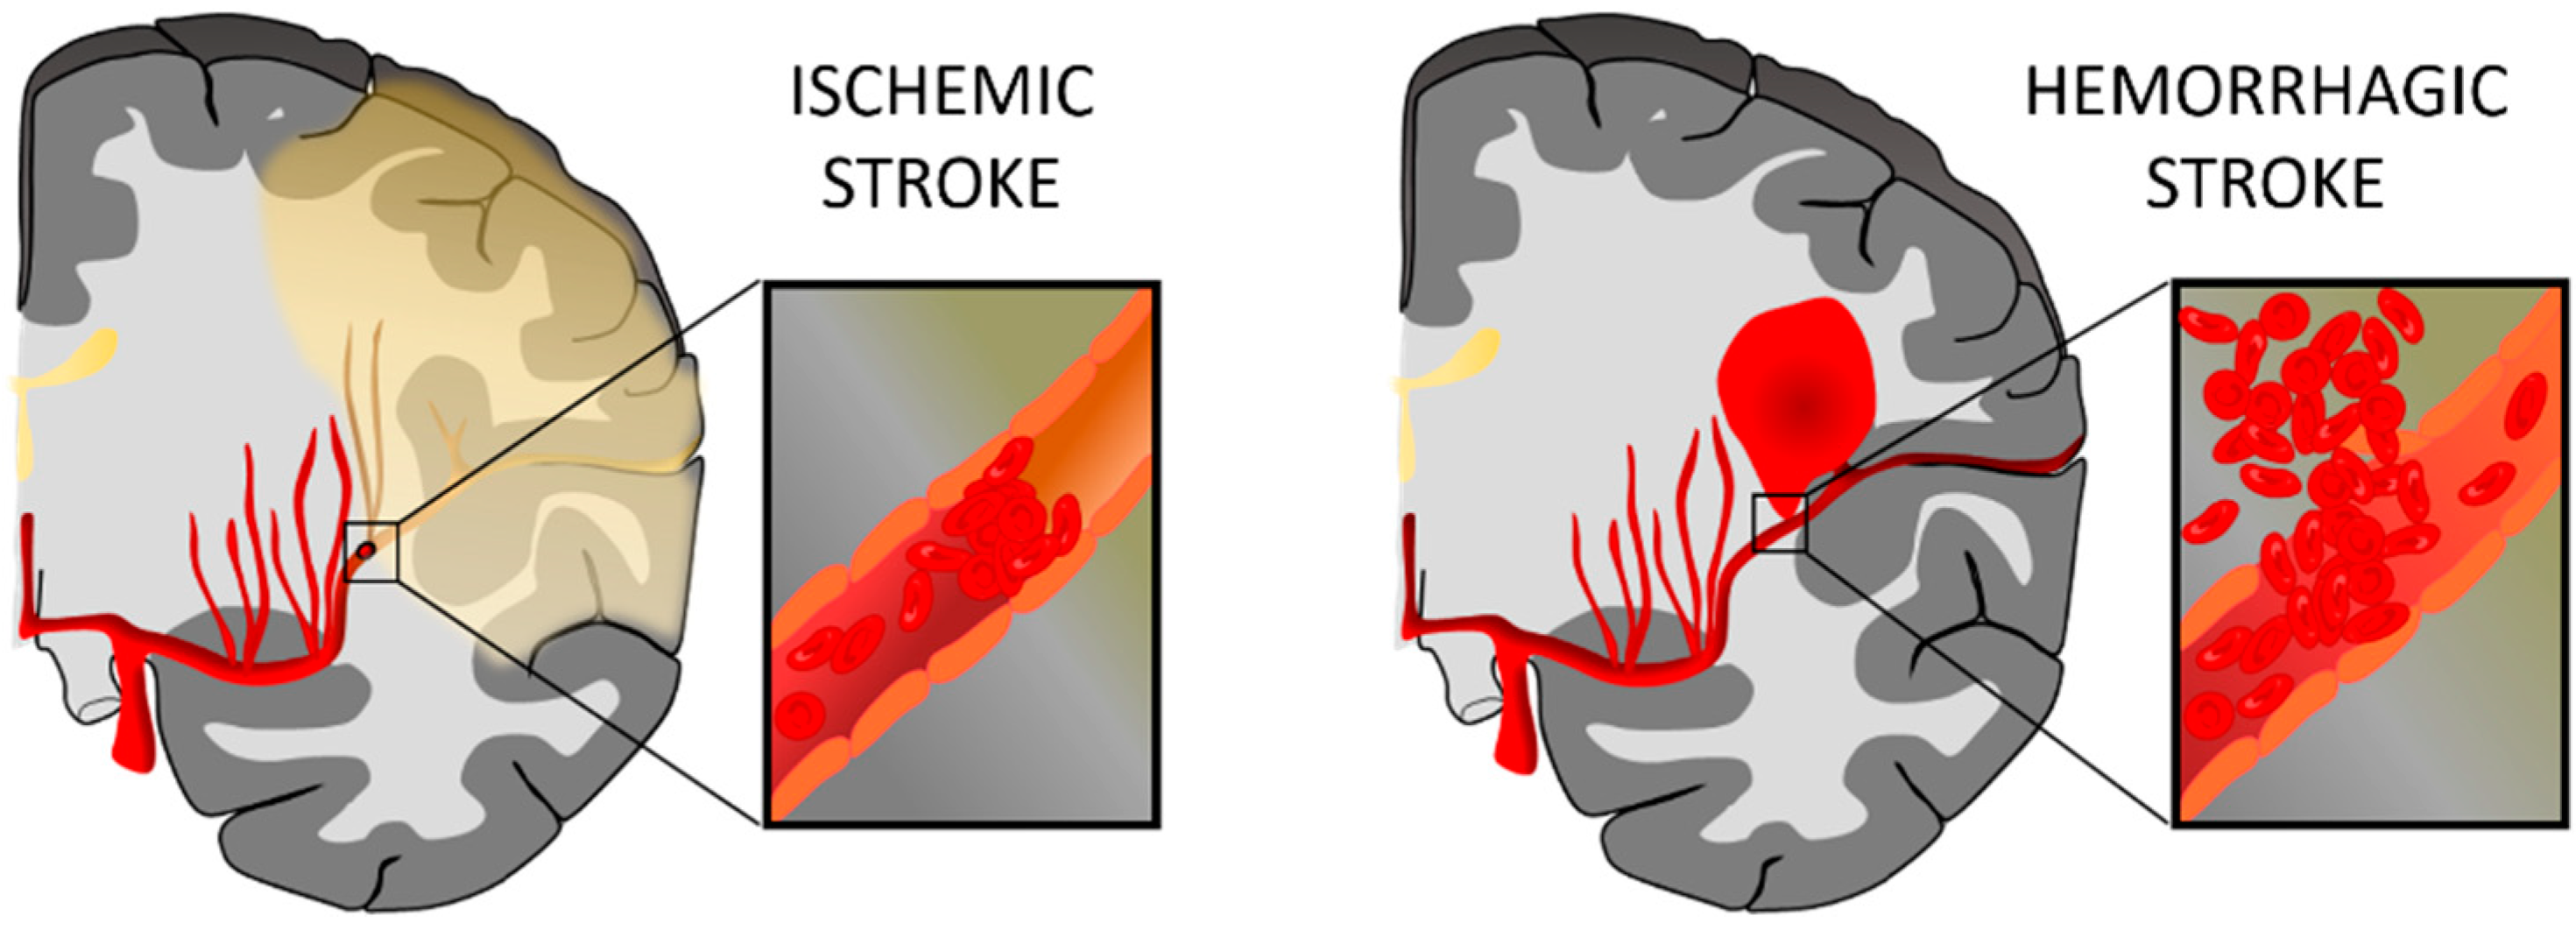

1.1. Stroke